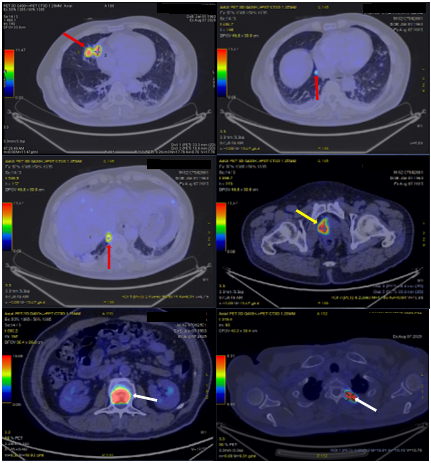

Bệnh nhân được chụp cắt lớp vi tính vùng tiểu khung, phát hiện khối u tại thùy phải của tuyến tiền liệt. Sau đó, bệnh nhân đã được chụp phim cộng hưởng từ nhằm đánh giá chính xác tính chất khối u (Hình 1).

Hình 1: Hình ảnh nốt vùng chuyển tiếp lệch phải (PIRADs 3) trên phim cắt lớp vi tính (mũi tên đỏ) và trên phim cộng hưởng từ (mũi tên vàng).

Sau đó, bệnh nhân được bổ sung các xét nghiệm đánh giá toàn thân. Kết quả phim chụp cắt lớp vi tính ngực và bụng cho thấy, không chỉ có khối u ở tuyến tiền liệt mà bệnh nhân còn có nhiều khối u khác ở phổi (Hình 2), tuyến thượng thận (Hình 3) và xương (Hình 4).